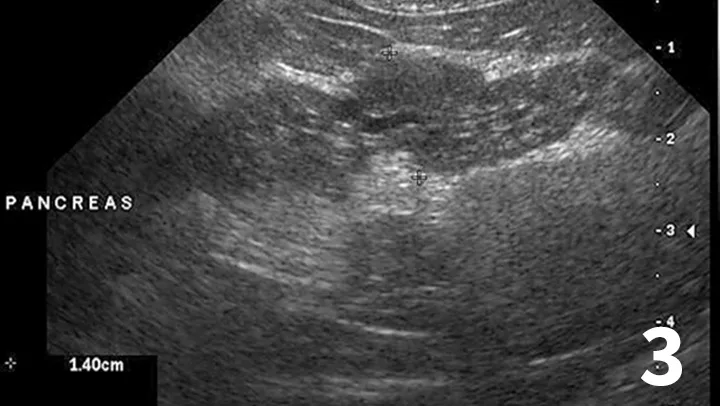

Assess for inflammatory bowel disease

• Abdominal ultrasound with careful evaluation of intestinal wall layering:

• Specific changes include thickening of the muscularis propria layer with or without concurrent thickening of the submucosal layer (Figure 4)

• Determine whether normal intestinal architecture is preserved because loss of layering is more consistent with intestinal lymphoma (large cell)20,21

• Evaluate regional lymph nodes carefully for size and echogenicity. Large hypoechoic lymph nodes are supportive of lymphoma

Figure 4

Ultrasound of the small intestine showing concurrent thickening of the muscularis propria layer and submucosal layer commonly seen in patients with IBD and small cell lymphoma.